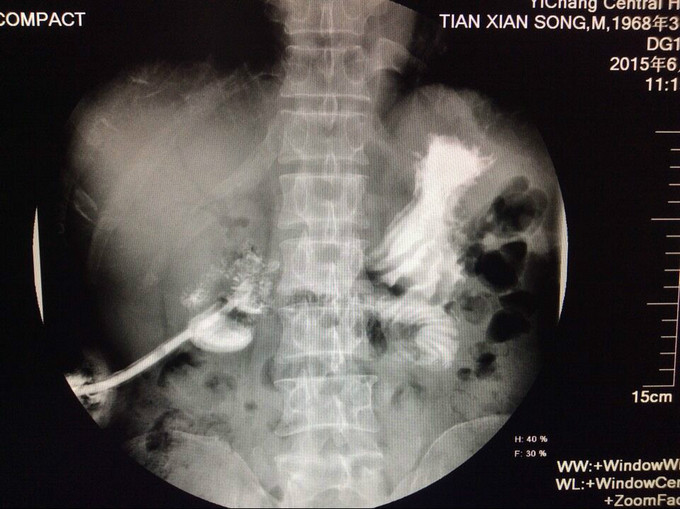

主诉:方向盘伤,胰头十二指肠破裂,肝十二指肠韧带撕裂伤术后8月,复杂肠漏1例。 2.现病史:患者因8月前因腹部外伤,当地医院行剖腹探查术,术中发现胆管、胰管、十二指肠损伤,肠系膜上静脉撕裂,行胰十二指肠切除,胰肠+胆肠+胃空肠Y吻合。术后出现重度感染休克、外伤性胰腺炎,予以腹腔引流术+空肠造瘘置营养管术,行抗休克、抗炎治疗,现术后8月腹腔引流管持续引流出胆汁及肠液,经引流管造影可见造影剂流入肠管,行上消化道造影未提示胃及肠管穿孔。

入院查血: Blood-Rt(五分类): 白细胞 6.97*10^9/L,红细胞 3.84*10^12/L,血红蛋白 122 g/L,红细胞压积 37.3 %,血沉 42 mm/h 查体:无特殊异常,腹腔引流管偶有黄褐色浑浊液体流出,量约50-80ml,腹软,无压痛、反跳痛,二便正常。 辅检:上腹部CT提示:胆肠吻合口一直径约2cm结石 辅助检查见上图

漏口位置,依据上消化道钡餐造影未见消化道穿孔,而从腹腔引流管处注入碘水造影可见肠管及隐约胃形显示,估计漏口位置为胰腺空肠及胆管吻合处肠管漏口, CT提示:胆道结石,尝试拔管后漏口无法愈合,再次予以腹腔引流置管。 我们分析漏口无法愈合的原因为胰液及胆汁对自身组织的消化,术中胆肠吻合口处放置T管,及胰腺空肠段放置引流管,引流肠液,目的为减轻消化液对漏口的影响,术后原漏口愈合,但出现新唇状漏,采用T管经皮下隧道引流 ,原皮肤漏口缝闭,同时加用负压吸引。 讨论2点: 1.该病人初次少量胆漏合并胆道结石时是否需要手术治疗? 2.再次出现唇状漏时,患者消化液外漏引起局部皮炎,皮肤伤口周围组织腐蚀严重,采用T管经皮下隧道引流,能否起到良好的治疗效果?